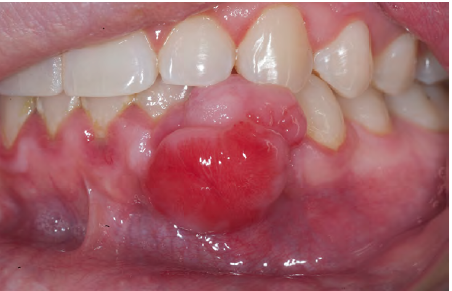

What is this clinical finding?

Pyogenic Granuloma:

Pyogenic Granuloma

Histology

They are filled with blood vessels so they’re very very rich

in vascularization > they tend to bleed easily